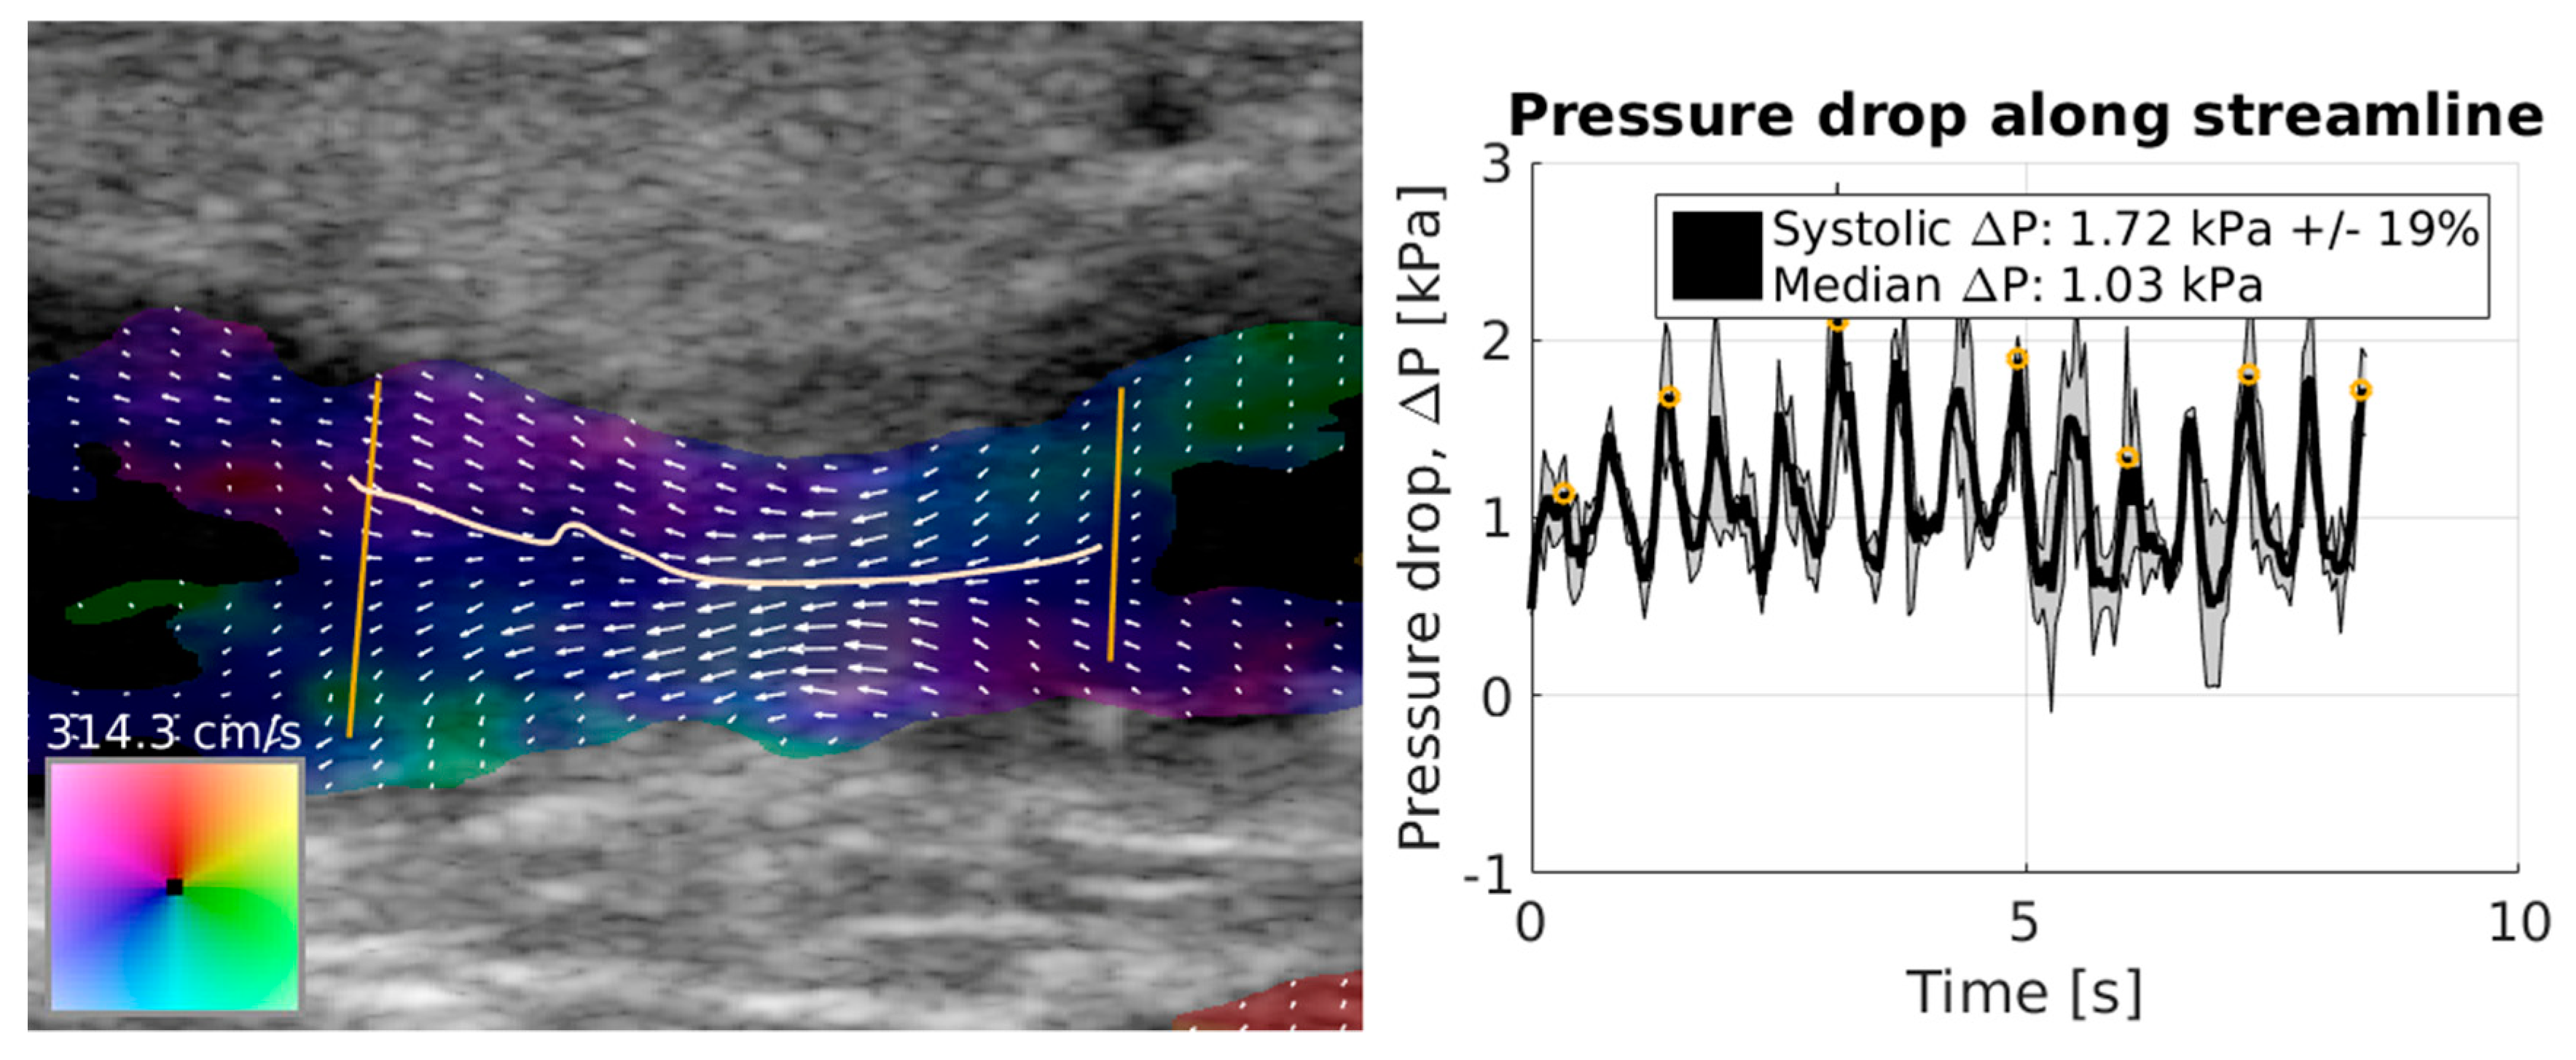

- Olesen, J.B.; Villagomez-Hoyos, C.A.; Moller, N.D.; Ewertsen, C.; Hansen, K.L.; Nielsen, M.B.; Bech, B.; Lonn, L.; Traberg, M.S.; Jensen, J.A. Noninvasive Estimation of Pressure Changes Using 2-D Vector Velocity Ultrasound: An Experimental Study With In Vivo Examples. IEEE Trans. Ultrason. Ferroelectr. Freq. Control 2018, 65, 709–719. [Google Scholar] [CrossRef]